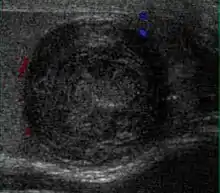

Embryonal cell carcinomas, a more aggressive tumor than seminoma usually occurs in men in their 30s. Although it is the second most common testicular tumor after seminoma, pure embryonal cell carcinoma is rare and constitutes only about 3 percent of the nonseminomatous germ cell tumors. Most of the cases occur in combination with other cell types. At ultrasound, embryonal cell carcinomas are predominantly hypoechoic lesions with ill-defined margins and an inhomogeneous echotexture. Echogenic foci due to hemorrhage, calcification, or fibrosis are commonly seen. Twenty percent of embryonal cell carcinomas have cystic components. The tumor may invade into the tunica albuginea resulting in contour distortion of the testis [Fig. 4].